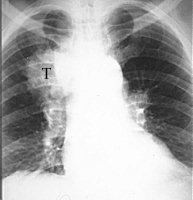

A CAT (Computer Aided Tomograghy) or CT (Computed Tomography) scan uses an x-ray source to measure the non-translucency of the slice of an object. Numerous one-dimensional projections are taken under different angles. From those projections a 2-D intensity distribution is calculated throughout the slice. This results in an image that gives an impression about the inside of an object. The newest types of Spiral CT for medical applications rotate the x-ray source around the patient while the patient is slowly moved through the machine. In 30 seconds, while the patient is holding his breath, a 3-D image of the chest is recorded.

The photo on the right is a regular x-ray photo of a chest with a tumor (T). The photo on the left is a CT scan straight through the tumor, which can now be seen clearly, as well as the metastases (N) next to it.